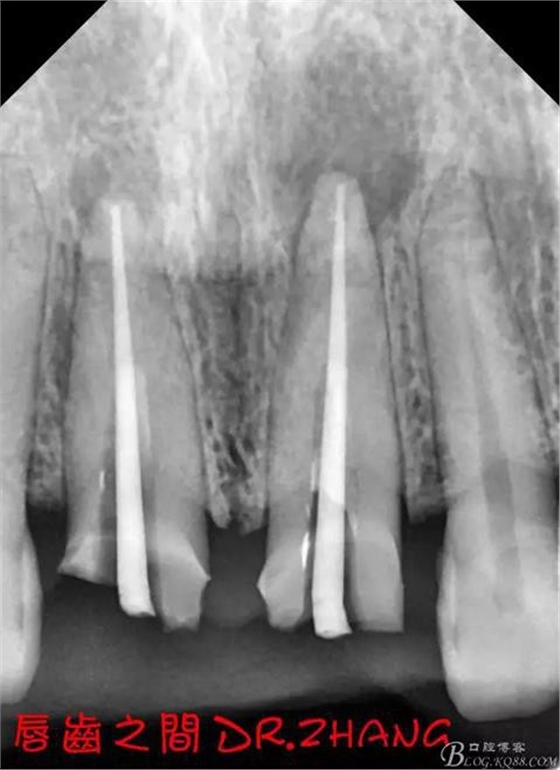

復(fù)診:腫脹明顯消失 患者自訴感覺(jué)良好 溝通后決定拆除11 21兩顆烤瓷冠后重新修復(fù) 去冠器直接去冠 去除11根管內(nèi)的充填物 15#K銼疏通根管 11 21根長(zhǎng)均為16MM平斷面 薩尼S3系統(tǒng)機(jī)擴(kuò)至2S 期間不斷用氯己定和鹽水交替沖洗 吸潮紙尖干燥根管后06 25#試尖

思博安熱牙膠系統(tǒng)根充 燙斷至根尖三分之一處后纖維樁恢復(fù)牙體組織